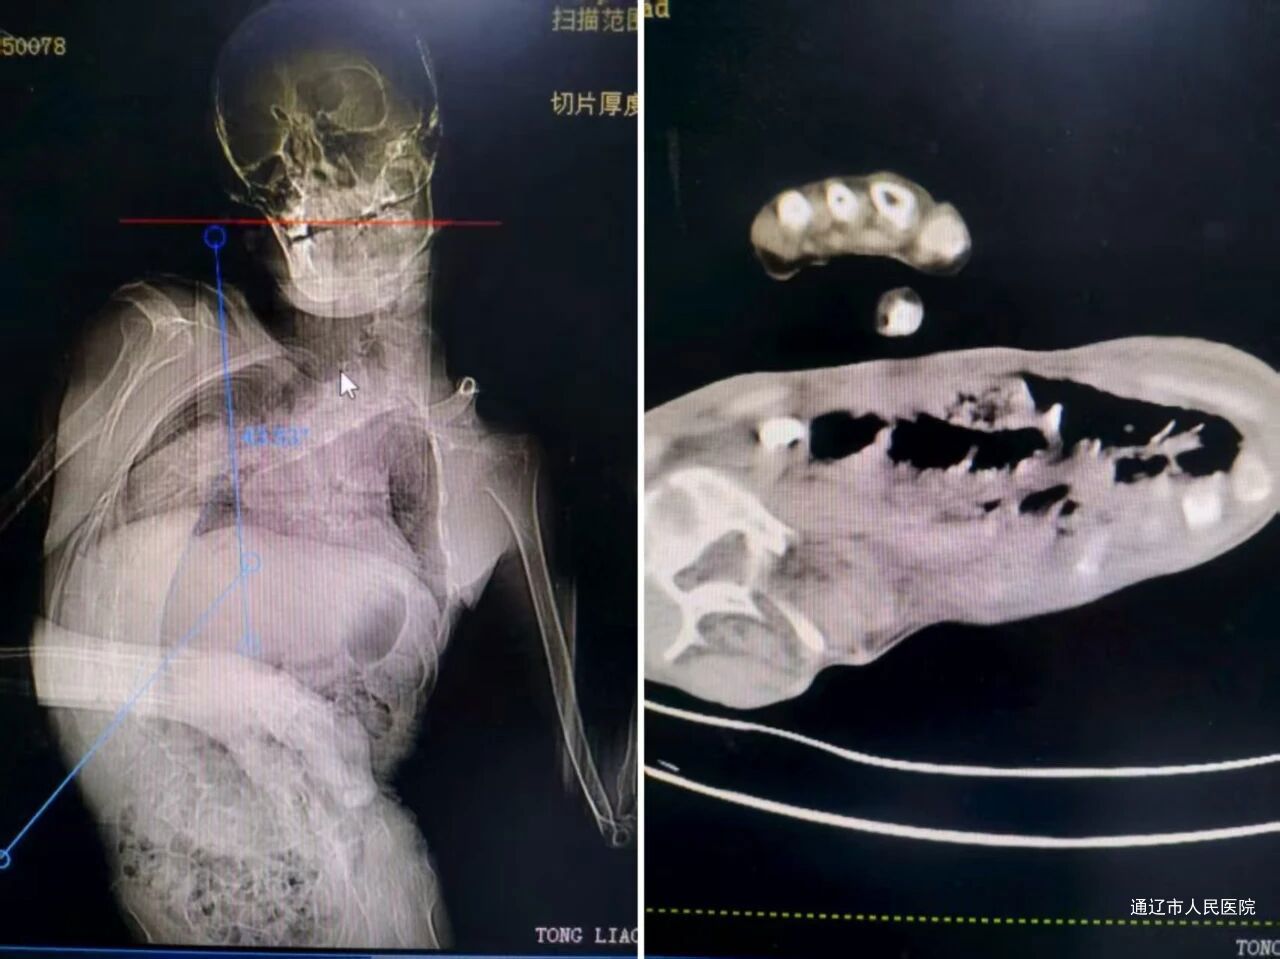

该患者为34岁男性,因“反复右侧腰腹部剧烈疼痛5天”入院。术前检查显示,其右输尿管上段存在一枚2.5×2.0cm结石,伴右肾中度积水,结石CT值达1200HU,且合并泌尿系感染,肾功能已受影响。更棘手的是,患者患有先天性脑性瘫痪、继发性重度胸腰椎后凸侧弯畸形,长期卧床致营养不良,胸廓严重挤压,无法耐受经皮肾镜碎石术(PCNL)的标准俯卧位——该体位可能直接导致患者通气功能障碍甚至循环衰竭,同时脊柱畸形使肾脏解剖位置严重移位、肋骨和髂骨遮挡常规穿刺路径,麻醉气道管理与手术操作空间均面临极大挑战。

针对此情况,泌尿外科主任徐志强牵头组织手术麻醉科、ICU开展多学科会诊(MDT),经反复模拟体位与风险评估,最终制定个体化手术方案:采用改良仰卧位,将患者右侧抬高约40°,用大量软垫、凝胶垫支撑胸腰部,既保障呼吸循环稳定,又为肾脏穿刺创造操作条件;手术麻醉科主任赵勇团队制定纤维支气管镜引导下气管插管方案,术中采用肺保护性通气策略,配备全面有创血流动力学监测,应对困难气道与通气风险;以PCNL为首选方案,同时备好输尿管软镜钬激光碎石术(RIRS)作为备用。

术中,在超声实时引导下,徐志强团队精准穿刺目标肾盏-肾盂,建立操作通道。但术中发现,患者肾脏旋转移位与肋骨遮挡导致肾镜无法顺利通过迂曲狭窄的输尿管管腔,继续操作可能引发脏器损伤。徐志强当机立断,决定转为RIRS技术:通过已建立的经皮肾通道,顺利置入F12输尿管软镜鞘,利用软镜灵活多角度的优势,逐步突破输尿管狭窄段。随后采用钬激光以“粉尘化+碎块化”结合策略击碎结石,用套石篮取出较大碎块,较小粉末随冲洗引流自然排出。整场手术耗时70分钟,术中出血仅约2ml,无任何并发症,患者生命体征全程稳定。